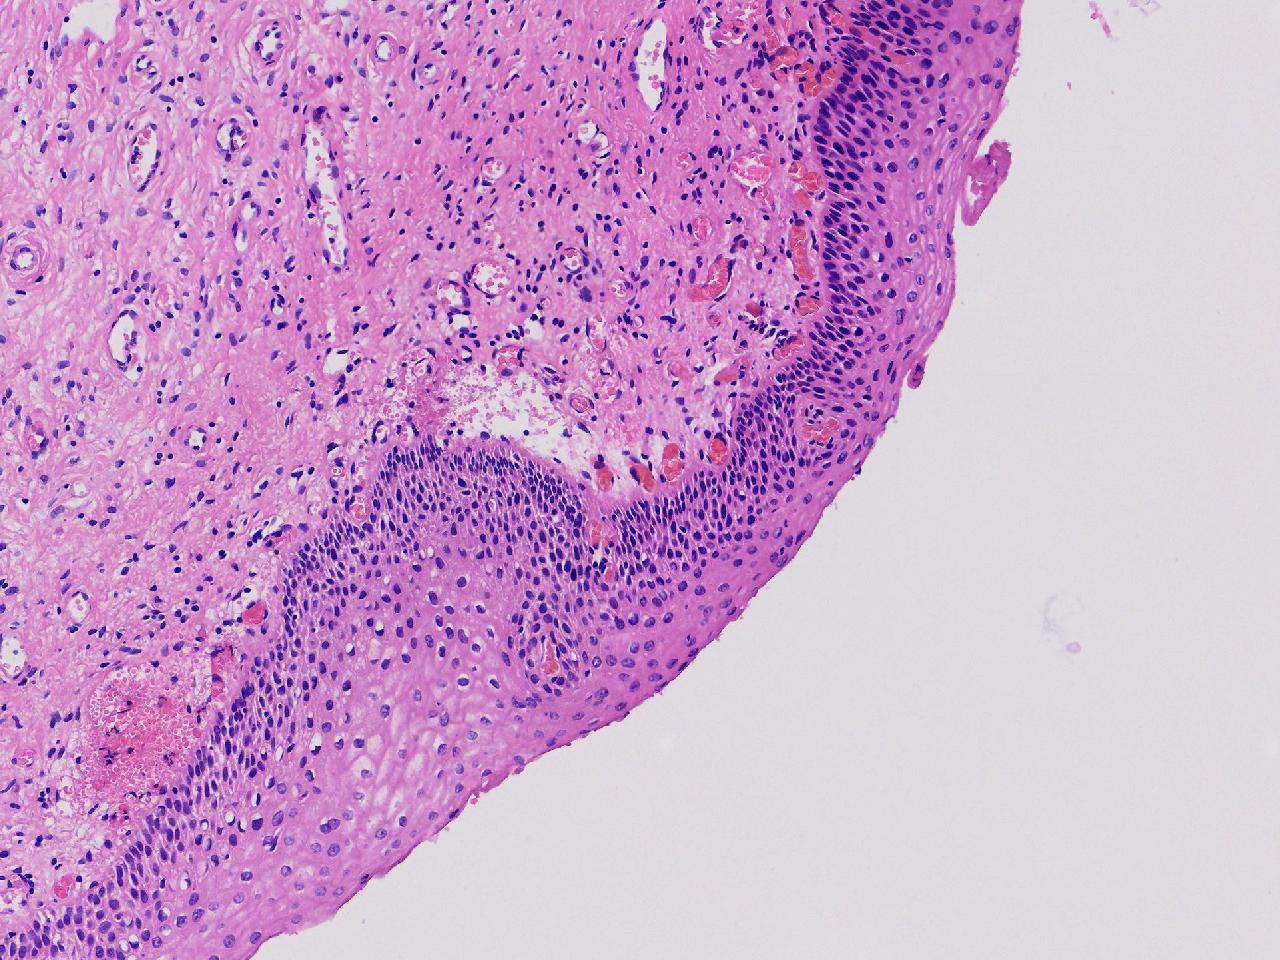

CIN1级? CIN2级?

性别年龄61岁临床诊断

一般病史女,61岁,宫颈活检,,HPV6+ 52+

标本名称宫颈活检

大体所见灰白色不整形软组织1块,直径0.3厘米。

CIN2倒是不够,图3有几个像挖空细胞,HPV有阳,勉强可以考虑小灶LSIL。

• zhuang xia nan:  是的。  2级肯定不够,有挖空细胞,小灶1级。    谢谢老师指点。

CIN1.